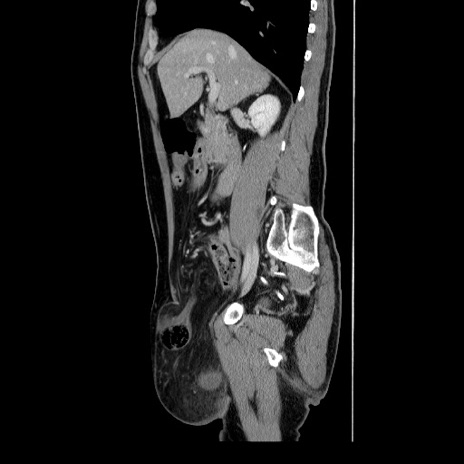

症例34(矢状断像)

冠状断像